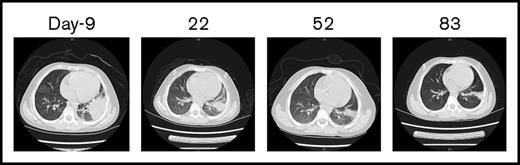

The CBC recovery was accompanied by disappearance of allo–CAR-T cells and increased MRD. Therefore, a second CAR-T course from her own source was initiated. At time of apheresis, the collected cells were 100% of her own based on genotyping, with an absolute lymphocyte count of 0.97 × 109/L and 45% CD3 T cells. Cyclophosphamide 400 mg/m2 and fludarabine 30 mg/m2 conditioning regimen was given on day 51, and autologous CAR-T cells (0.16 x 106/kg) were infused on day 56, which was well tolerated. CAR-T–cell expansion was detected on day 64, and the patient received etanercept for an associated fever. Her temperature returned to normal by day 66. On day 78, 23 days after the auto–CAR-T infusion, BM examination indicated CR by histology and flow cytometry (Figure 2D). Chromosomal analysis showed complete normal phenotype (46, XX) without abnormal clones. Computed tomography (CT) scans of lungs revealed complete resolution from previous infections by day 83 (Figure 3). Because of the lack of matched unrelated donor, and a negative test result for donor specific antibody, the patient subsequently underwent haploidentical hematopoietic stem cell transplantation from the same donor 2 months after the auto–CAR-T infusion.

CT scans of the chest before and after allo–/auto–CAR-T infusions. Before CAR-T treatment, CT scans revealed severe infections (day −9), which gradually resolved after allo– and auto–CAR-T infusions (days 22, 52, and 83).

CT scans of the chest before and after allo–/auto–CAR-T infusions. Before CAR-T treatment, CT scans revealed severe infections (day −9), which gradually resolved after allo– and auto–CAR-T infusions (days 22, 52, and 83).